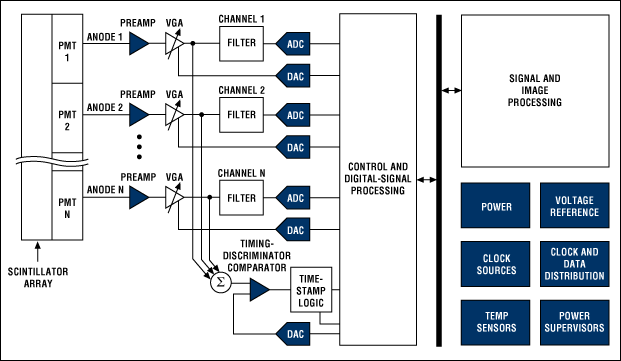

A circular detector contains scintillators that feed photomultiplier tubes (PMTs). Each PMT will typically be fed by more than one scintillator (see Figure 3). Because the PMTs will not be exactly matched, a variable-gain amplifier (VGA) is needed to tune the signal from each one. Each VGA requires a DAC to convert the digital control signal into the appropriate voltage. The signal can then be low-pass filtered before being digitized by a 10- to 12-bit ADC sampling around 50 to 100 Msps (see Figure 4). The entire chain must be highly accurate and low-noise, while keeping power under control and components small and compact. Analog Devices recommends their AD8332 VGA as one option for trimming the PMT signals before sending them through the filter to a AD9230 12-bit ADC, which can sample at up to 250 Msps.

Figure 4: Block diagram for a PET system (Courtesy of Maxim).

The timing is critical. Each signal gets a timestamp, and the timestamps are compared to see if two opposing events coincide. On newer systems, the timestamp is accurate enough to locate the source of the event. Maxim has a number of comparators that can serve here, including the MAX9601; their MAX5661 16-bit DAC can be used to set the comparator reference.